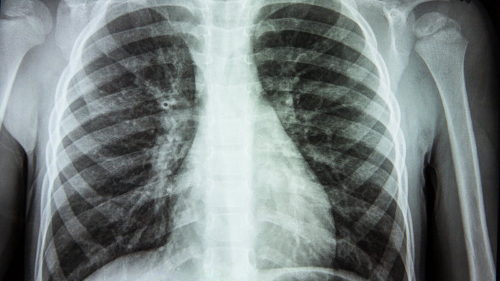

1. 흉부 X-ray 촬영

폐암 검사방법 중 가장 일반적인 검사의 하나로 엑스레이 촬영이 있습니다. 가장 기초적인 검사이고 가장 빠르기도 합니다. 하지만 이 방법은 폐암 세포가 5mm 이상 자란 상태에서 발견할 수 있습니다. 때문에 극 초기의 경우에는 발견하기가 어렵다고 합니다. 또한 흉부 X-ray 촬영은 심장 주변부나 뼈와 겹치는 부분은 확인이 어려울 수 있습니다.